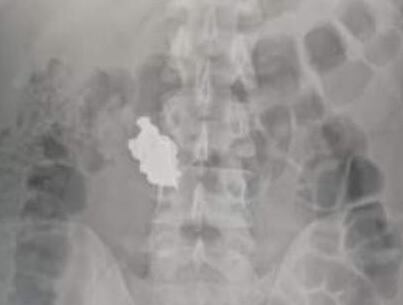

Faulkner fue llevado al hospital Calderón Guardia a las 8 de la noche y ahí le hicieron la placa que determinó que tenía el objeto robado en su estómago.

Las autoridades debían esperar a que la expulsara para aportarla como evidencia.